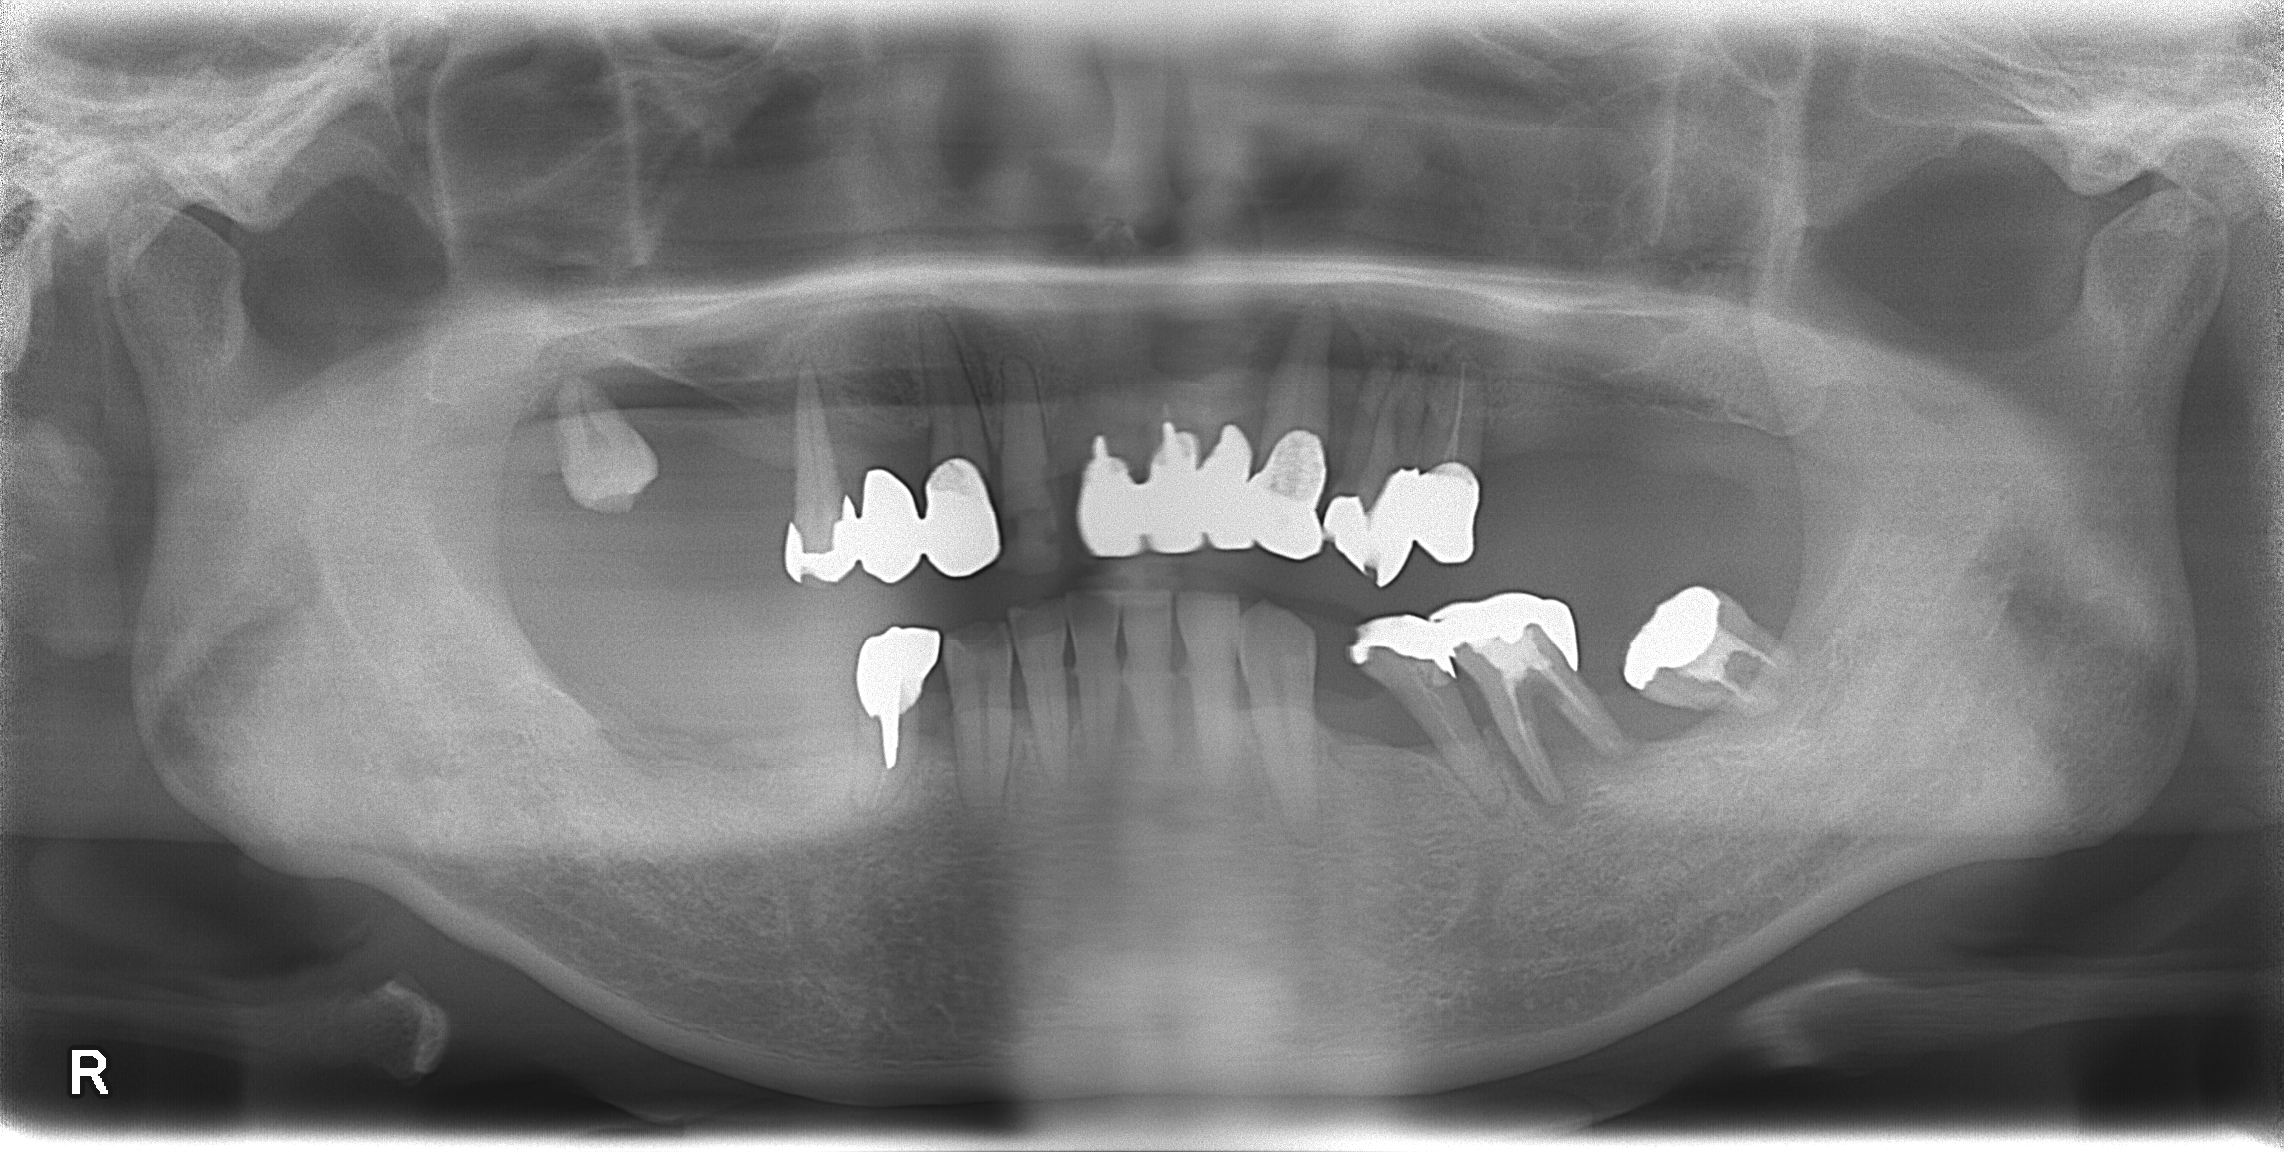

治療前(CT)

CT画像でインプラントの診断をして何回かに分けて9本埋入しました。

上の両奥歯、前歯、右下の奥歯を歯周病で失っておられました。左下の奥歯も揺れが大きかったので残すのが難しい状態でした。